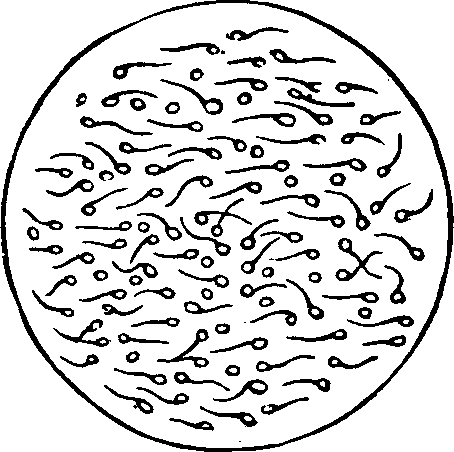

Chronic inflammation of the vagina also gives rise to acrid secretions, which destroy the vitality of the spermatozoa. Suppression of the menses, or any disorder of the uterine functions, may disqualify the female for reproduction. Flexions of the uterus, displacements, congestions, and local debility, may likewise prevent fertility. Sterility may result from impaired ovarian innervation or undue excitement of the nerves, either of which deranges the process of ovulation. Even too frequent indulgence in marital pleasures sometimes defeats conception. Prostitutes who indulge in excessive and promiscuous sexual intercourse, seldom become pregnant. Any thing that enfeebles the functional powers of the system is liable to disqualify the female for reproduction.